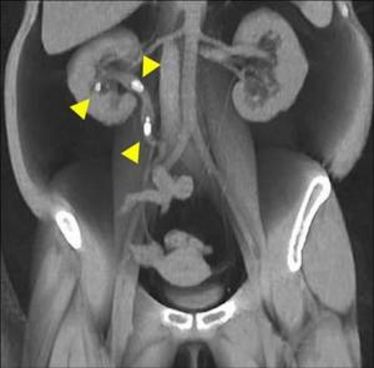

22.09.2011

MR aktuell

MR aktuell

22.09.2011

MR Aktuell 2011

MR Aktuell 2011